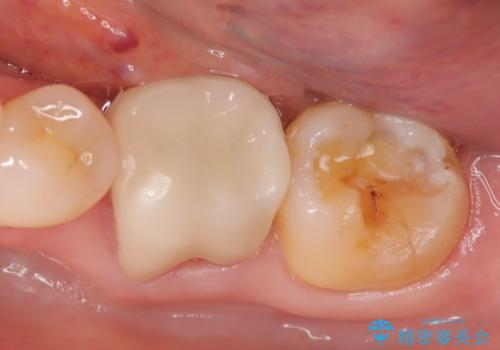

プラスチックが欠けた。

- 奥歯の咬合面のプラスチックが欠けたことを主訴に来院されました。

金属での修復も提案しましたが審美的な希望から

セラミックインレーでの修復を行うことになりました。

セラミックインレーは金属よりも歯を削って厚みを確保する必要があります。